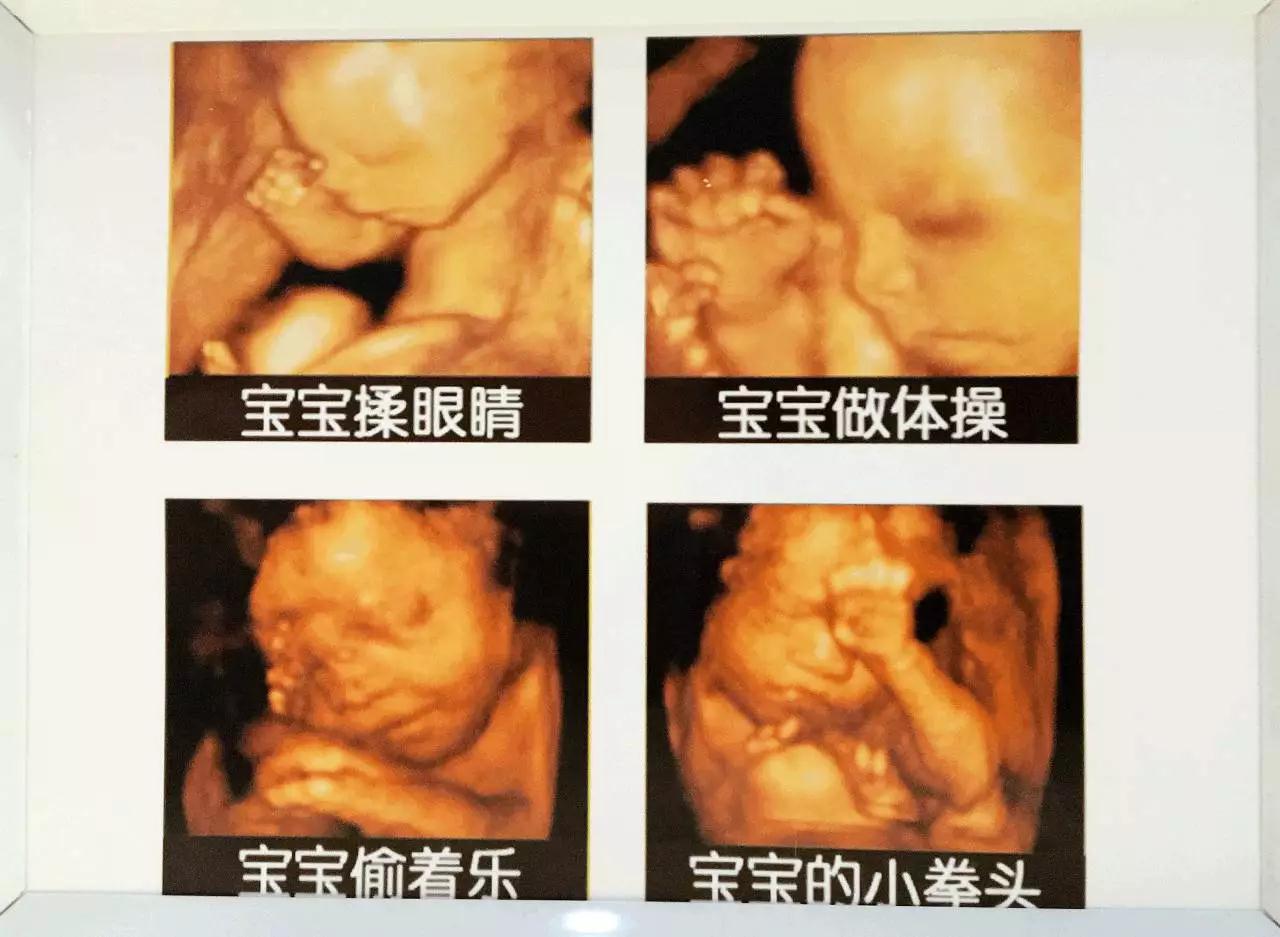

可见

胎宝宝在妈妈肚子里

经过了段非常奇妙的旅程

胎宝宝在妈妈肚子里的日常

“遇·见”四维艺术展

给你场

穿越时空的亲子艺术之旅